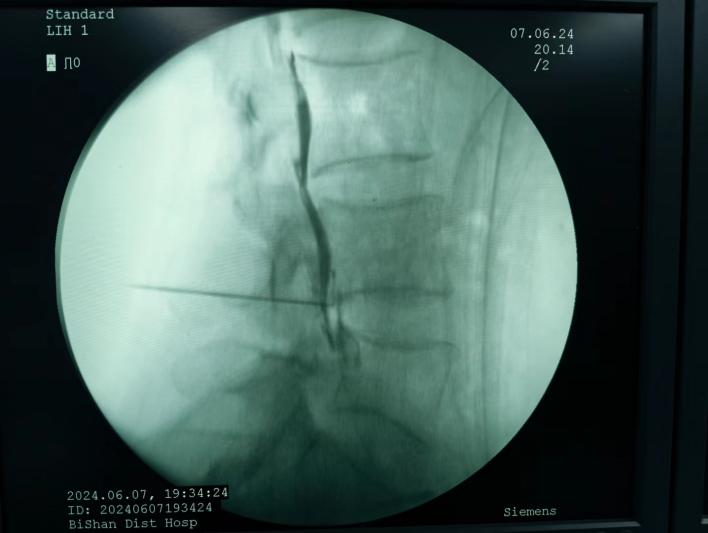

ac874aa18aee42e58f8890dd86cc1a27.Jpeg  09566eb81ad84804af008e90e5297638.Jpeg

椎間盤射頻消融術(shù)、膠原酶椎間盤化學(xué)消融術(shù)